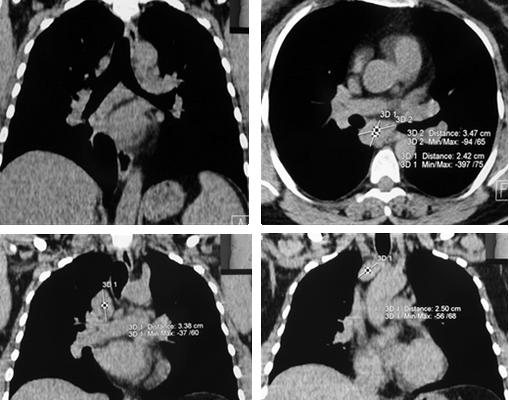

Рис. 1. РК-томограммы (медиастинальное окно) пациентки Е., 39 лет. Отмечается увеличение ВГЛУ паратрахеальной, бифуркационной и бронхопульмональной групп

Внутригрудная лимфоаденопатия визуализировалась в 70-80% случаев. Наблюдалось преимущественно двустороннее увеличение внутригрудных лимфатических узлов (ВГЛУ). Причем паратрахеальные лимфоузлы увеличивались как симметрично с обеих сторон, так и односторонне, чаще справа. Левостороннее увеличение демонстрировали лимфоузлы аортопульмонального окна. В некоторых случаях отмечалось обызвествление ВГЛУ в виде пунктира, по типу «скорлупы ореха» или аморфное. Симптом внутригрудной лимфоаденопатии наблюдался как изолированно, так и в сочетании с изменениями в легочной ткани. На компьютерных томограммах в режиме медиастинального окна увеличенные узлы средостения визуализировались достаточно хорошо (рис. 1).